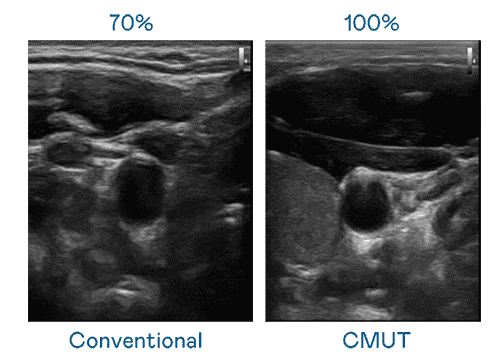

CMUT 技术是一种用电容式微机电元件来产生超音波讯号的技术。。。。与传统 PZT 压电式技术相比,,CMUT 频宽增加 30%,,,更宽频的超音波讯号让影像解析度大幅提升,,是实现高影像品质医疗超音波扫描、、、、促进精准医疗发展的关键技术。。。

超音波影像的解析度高低,,,,首先取决于探头能发出的讯号频宽。。。蓝狮在线 CMUT 可提供高清晰的超音波讯号,,,提供高频宽、、高灵敏度、、影像纹理细节更高的超音波影像,,协助医护人员缩短影像判读时间及利用精准的医疗影像进行诊断。。